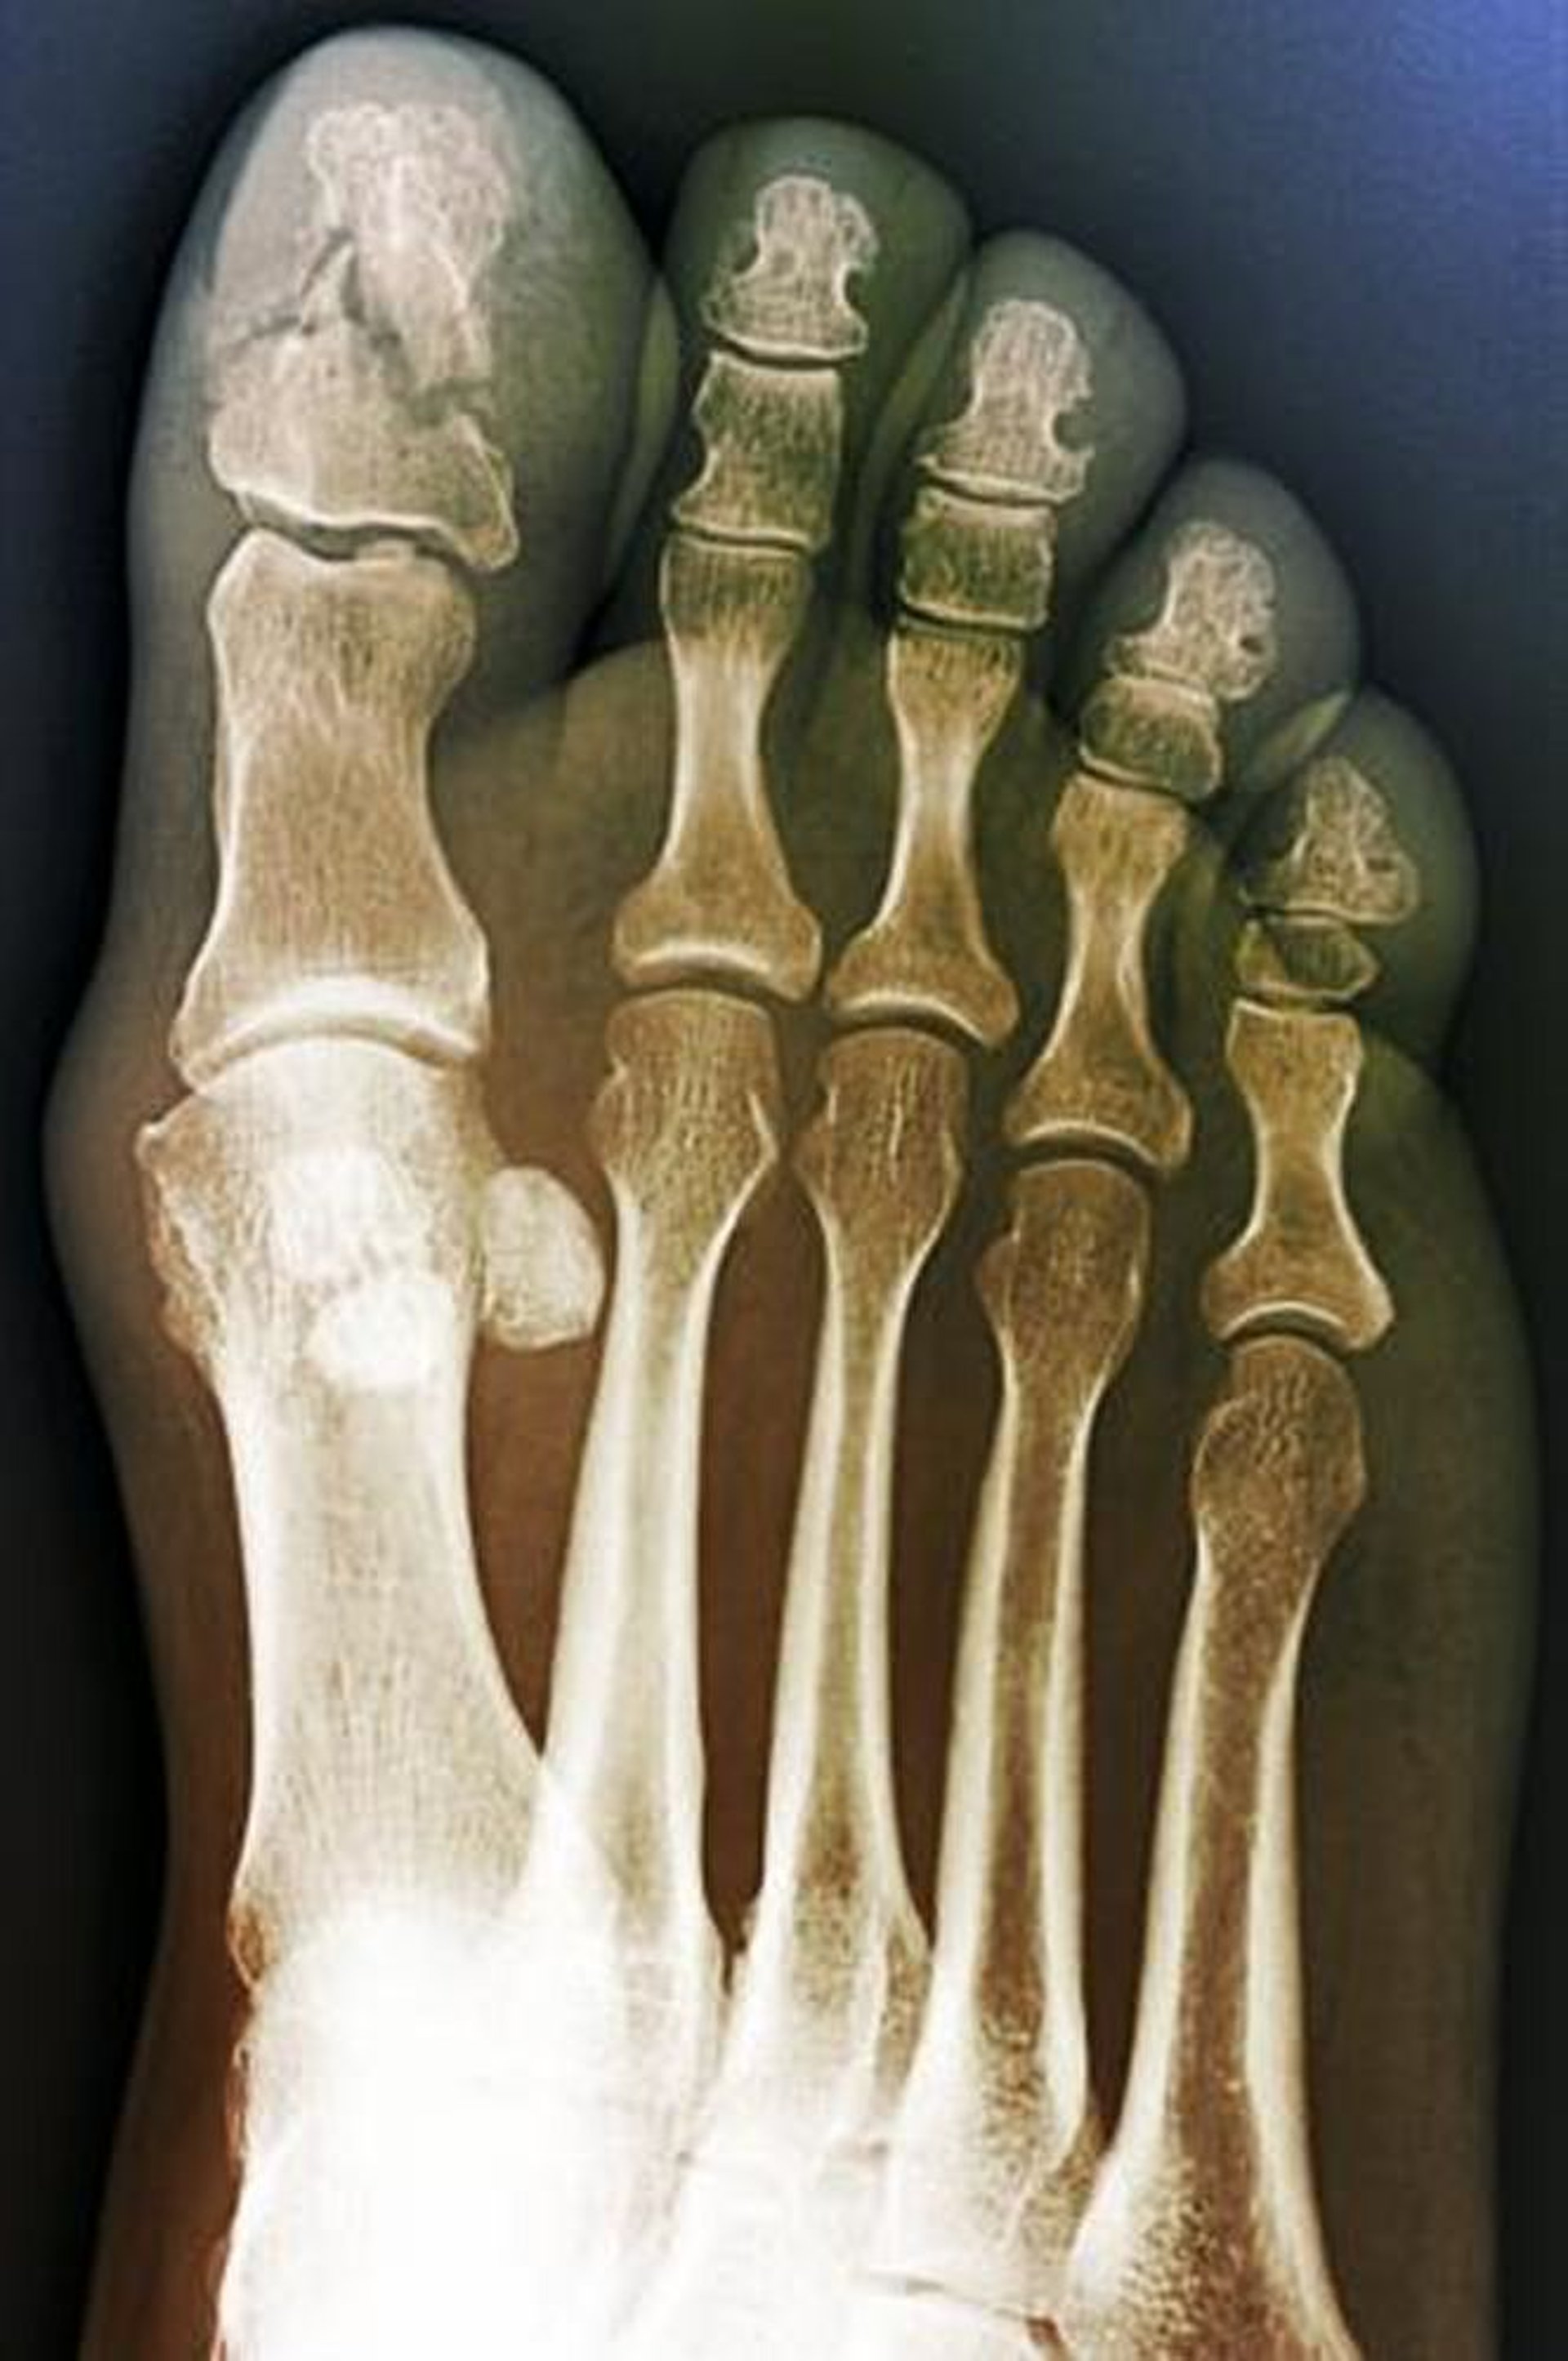

Fractura conminuta del dedo gordo del pie

Esta vista anteroposterior muestra una fractura conminuta de la falange distal del dedo gordo del pie. Este hallazgo sugiere un mecanismo de aplastamiento.

ZEPHYR/SCIENCE PHOTO LIBRARY